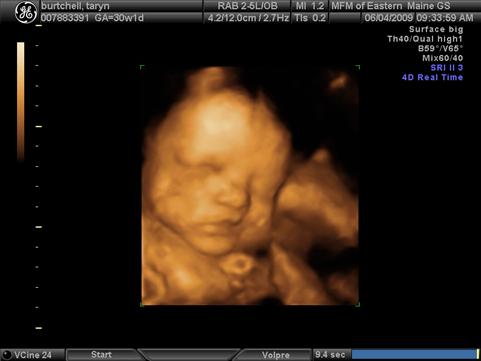

DH and i had our 3rd Level II 3D ultrasound and got to see baby Lauren again. She is doing great. Her left kidney has improved to normal developmental status and her right kidney is just under the cut-off to be considered normal, so it looks like her kidneys will be just fine. We go back in 6 weeks instead of 4 just to double check since it will be 3 weeks before she is due to arrive. She is 3.5 pounds exactly and is actually measuring a little on the big side, they said she is measuring in the 53rd percentile. She is still currently head down, basically in birthing position and has turned into a little gymnast with both feet by her head. The ultrasound tech said "it looked like she was picking her nose with her big toe" which you can see in one of the pictures. She has some shubby little cheeks!! And she has hair, DH and i weren't expecting that because we were both very bald babies so we are excited for some hair too!!

The first picture is the one with her big toe by her nose. I also added a new belly pic since i haven't taken one in a while. Image Attachment(s):